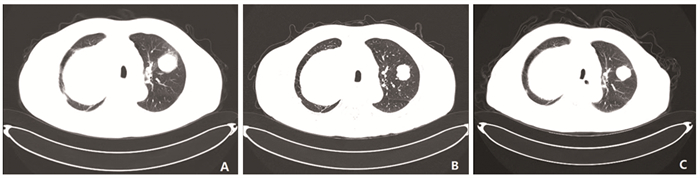

Competing interests: The authors declare that they have no competing interests.利益冲突声明:所有作者均声明不存在利益冲突。作者贡献:赵晓欢:收集临床资料,查阅文献及撰写论文乔慧、张静、窦郁:图片整理,指导论文写作及修改侯小明:指导研究方向 -